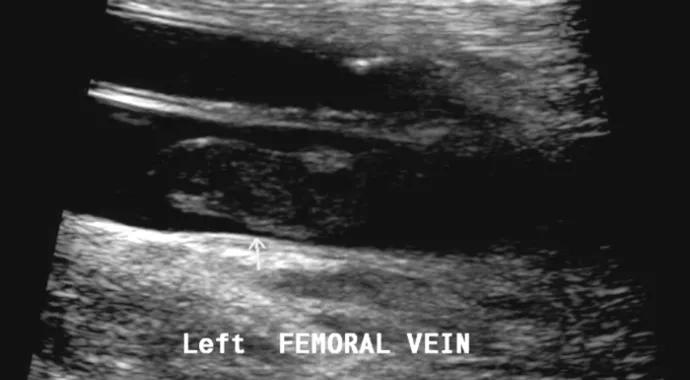

large blood clot 690×380

Working from what is probably the only center of its kind in the U.S., a multidisciplinary team at Cleveland Clinic is answering the call for a more efficient and effective approach to the diagnosis, treatment and monitoring of cancer patients who develop potentially deadly thrombosis.